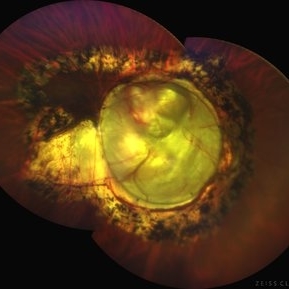

Chorioretinal coloboma involving disc and macula

Chorioretinal coloboma involving disc and macula

Mar 21 2022 by T. P . VIGNESH, MBBS,MS

Fundus photo of Right eye of a 55 year male patient revealing a fovea sparing well barraged chorioretinal coloboma involving the disc and the macula .

Photographer: Bharathi Singaravel

Imaging device: Zeiss Clarus

Condition/keywords: chorioretinal coloboma, coloboma of optic disc